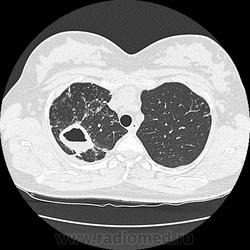

Ага, сначала вот эта с каверной пришла 12.05, а потом с туберкуломами 19.05 с интервалом в неделю, закон парных случаев, обе только родили, род.дом в панике, я в шоке

В том то и дело, что анамнез скудный, жалоб нет или врала, жила себе поживала девушка, забеременела, родила, а в правом легком "дырка".

Что касается женщины, то она не "врала". Беременность в данном случае была для неё, как лечебный pneumoperitoneum.